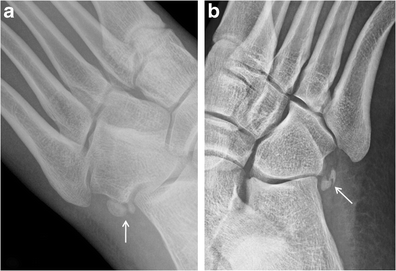

Osteoarthritis. Bone scan of the bilateral feet (a) shows nonspecific but intense tracer uptake localising to the medial hallucal sesamoid (arrows). Lateral radiograph at the first toe (b) reveals joint space narrowing and osteophyte formation at the medial sesamoid-metatarsal articulation (arrow), consistent with osteoarthritis